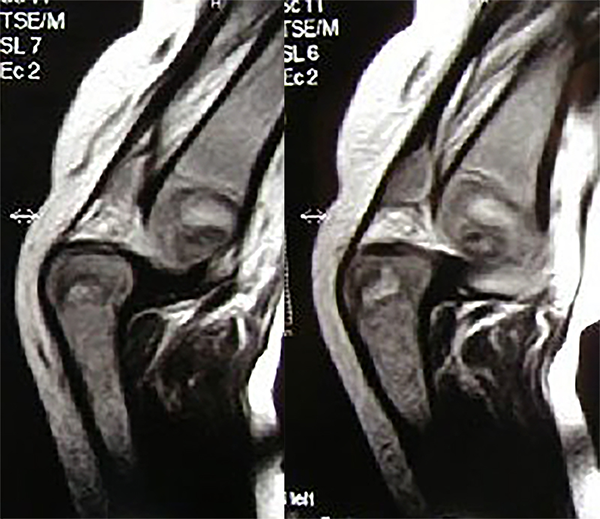

Figura 2: RM en la que se ve la luxación congénita de ambas rodillas.

En ese momento, a la edad de cuatro meses, es intervenido quirúrgicamente con reducción de ambas caderas por un abordaje inguinal del pectíneo, reducción de rodilla derecha luxada con cuadriceplastia en V-Y, y reducción quirúrgica del astrágalo vertical luxado, todo en el mismo acto quirúrgico (fig. 3).